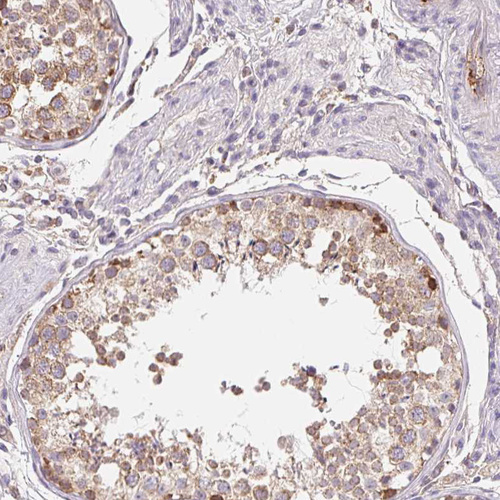

Immunohistochemical staining of human Fallopian tube moderate membranous positivity in glandular cells.